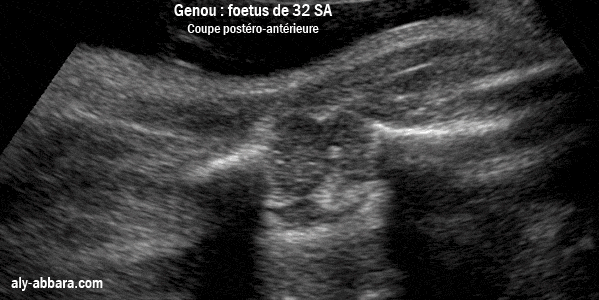

Image échographique montrant l'articulation du genou en extension

Fœtus de 32 semaines d'aménorrhée

• Sur cette image on distingue bien les principaux éléments formant l'articulation du genou, à savoir : l'épiphyse inférieure du fémur, et l'épiphyse supérieure du tibia ; ces deux épiphyses ne sont pas encore calcifiées, mais on peut remarquer la présence du point de l'ossification de l'épiphyse supérieure du tibia.

• La rotule est bien visible (malgré qu'elle n'est pas encore calcifiée), ainsi ses deux tendons (rotulien et quadricipital).